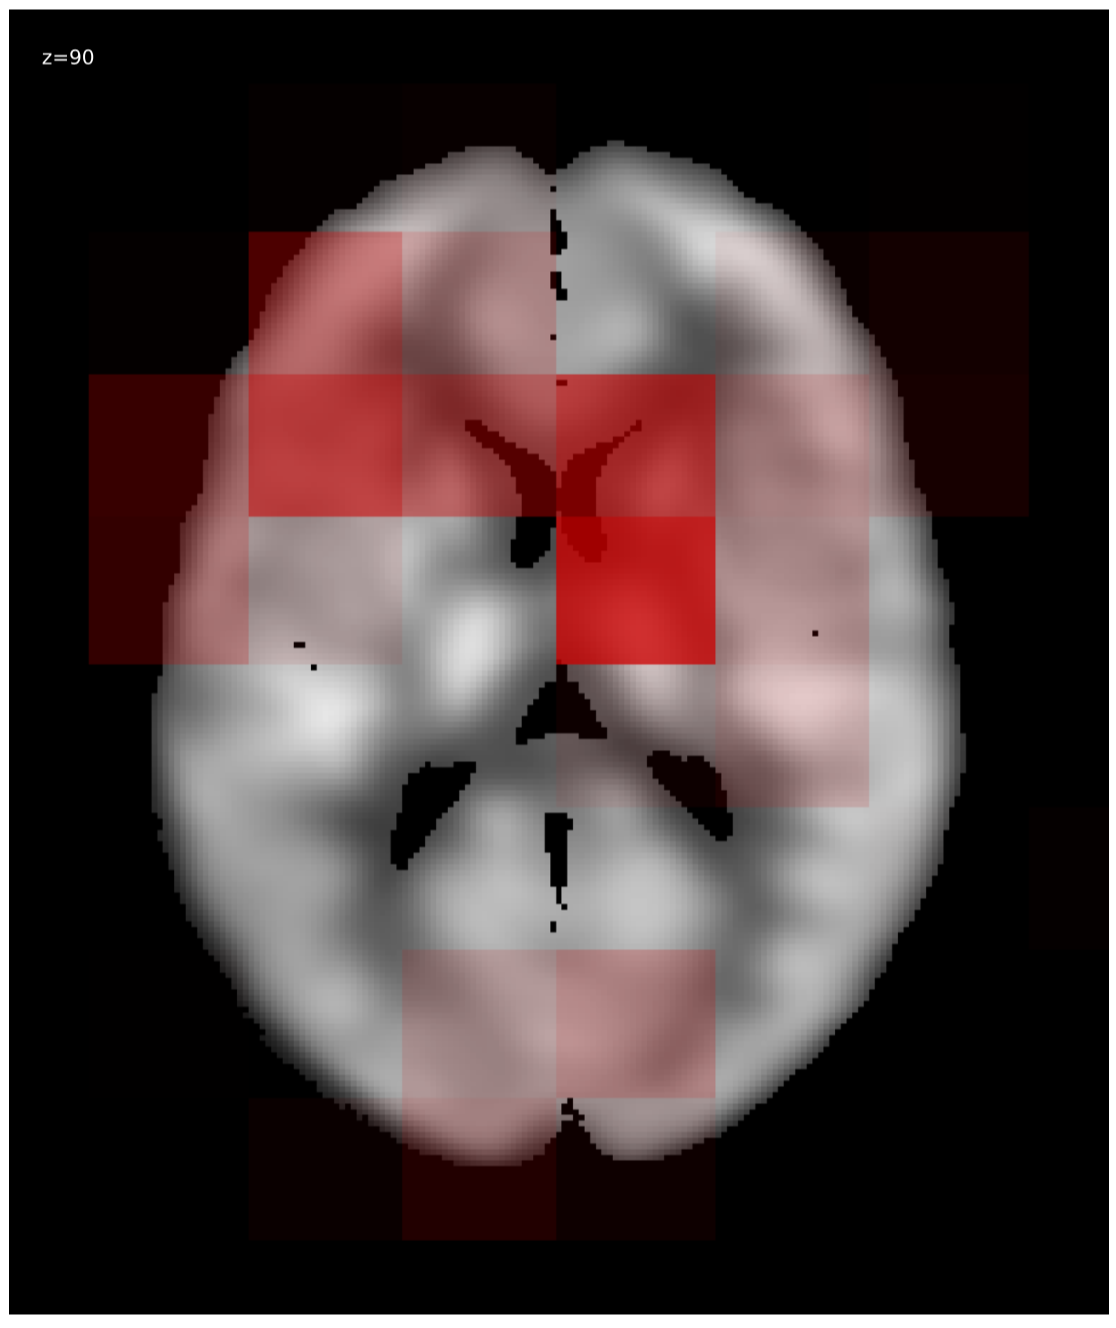

3.1 Visualization

We generated relevance heatmaps for all visualizations methods, averaged over AD PET images in the test dataset. Figure 2 presents the visual comparison of these five methods. The red areas/dots indicate that regions were important for the decision making of the 3D-CNN model. From the result, we can see that all the visualization focuses mostly on similar brain regions. There are some differences, such as the heatmaps generated for the gradient-based methods are distributed. The heatmaps highlight the areas that the CNN network is most susceptible. For the LRP method, the heatmap shows the average relevance of each voxel for contributing to the AD diagnosis score. The heatmaps generated by the occlusion based methods are more focused on the specific regions and cannot administer with large areas of distributed relevance. The reason behind the issue is the occlusion path was not able to cover those areas (for example, the cortex) completely. Brain area occlusion presents very high relevance for the temporal lobe. Since in this method, only one area is covered at a time, that can cause such high importance for one region and minimal relevance for other regions.